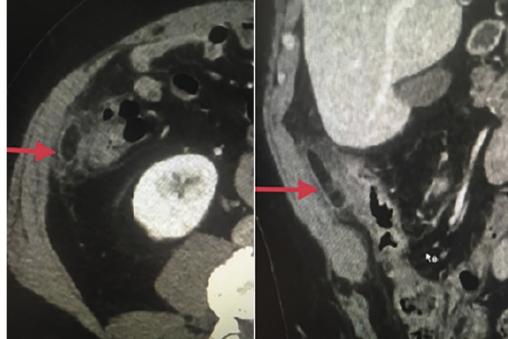

Le scanner abdominal montre une infiltration de la graisse péricæcale en regard d’une formation graisseuse ovalaire du bord antimésentérique du cæcum (c’est-à-dire en rapport avec la paroi abdominale ou les autres anses, le bord mésentérique adhérant au mésentère).

Diagnostic : appendagite latérocæcale.

L’exploration par tomodensitométrie (TDM) – qui fait le diagnostic de certitude – met en évidence une masse ovalaire adjacente au côlon et de densité plus élevée que la graisse péritonéale normale. À l’échographie, on retrouve le plus souvent un nodule non compressible et antérieur par rapport au côlon.